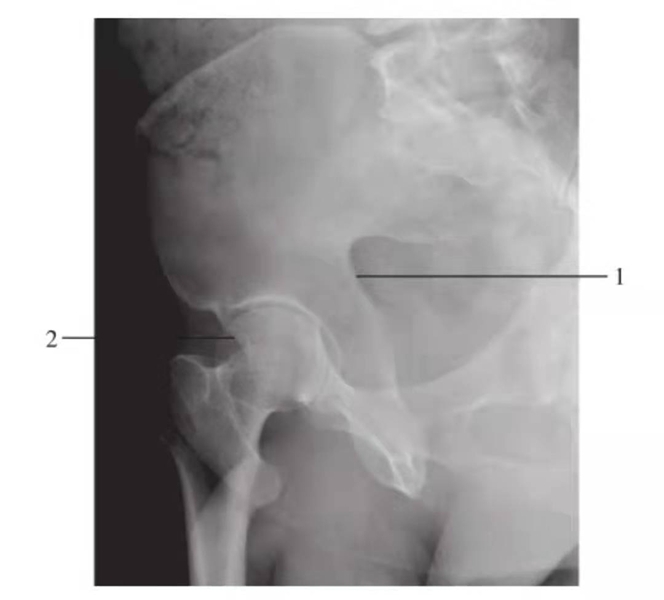

图2 髋关节正位片(成人期)

1.髋臼线;2.髂坐线;3.髂耻线;4.前唇线;5.后唇线;6.泪滴